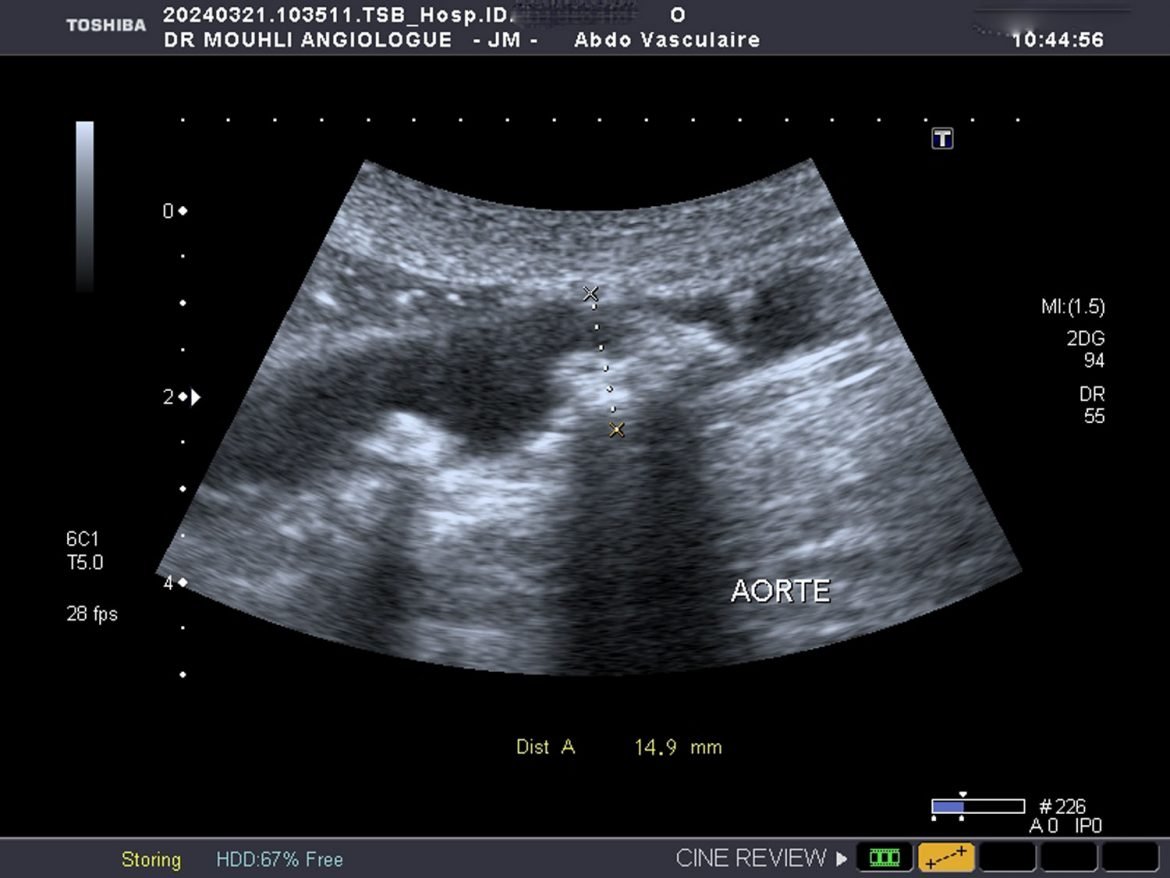

écho-Doppler artériel

Le diagnostic des thromboses aortiques présente une complexité notable, nécessitant une approche méthodique et l’utilisation de technologies d’imagerie avancées. Les thromboses aortiques, qui consistent en la formation de caillots sanguins dans l’aorte, peuvent entraîner des complications graves si elles ne sont pas identifiées et traitées rapidement. Les techniques diagnostiques les plus couramment employées incluent l’écho-doppler artériel et le scanner thoraco-abdominal injecté, chacune offrant des avantages uniques pour la détection des anomalies vasculaires.

L’écho-doppler artériel est souvent la première étape dans l’évaluation des thromboses aortiques. Cette technique utilise des ultrasons pour visualiser le flux sanguin et détecter toute obstruction ou anomalie dans l’aorte. L’écho-doppler permet non seulement de confirmer la présence d’une thrombose mais aussi d’évaluer sa taille et son emplacement précis. Toutefois, cette méthode peut être limitée par la qualité de l’image obtenue, surtout chez les patients ayant une anatomie complexe ou de l’athérosclérose avancée.